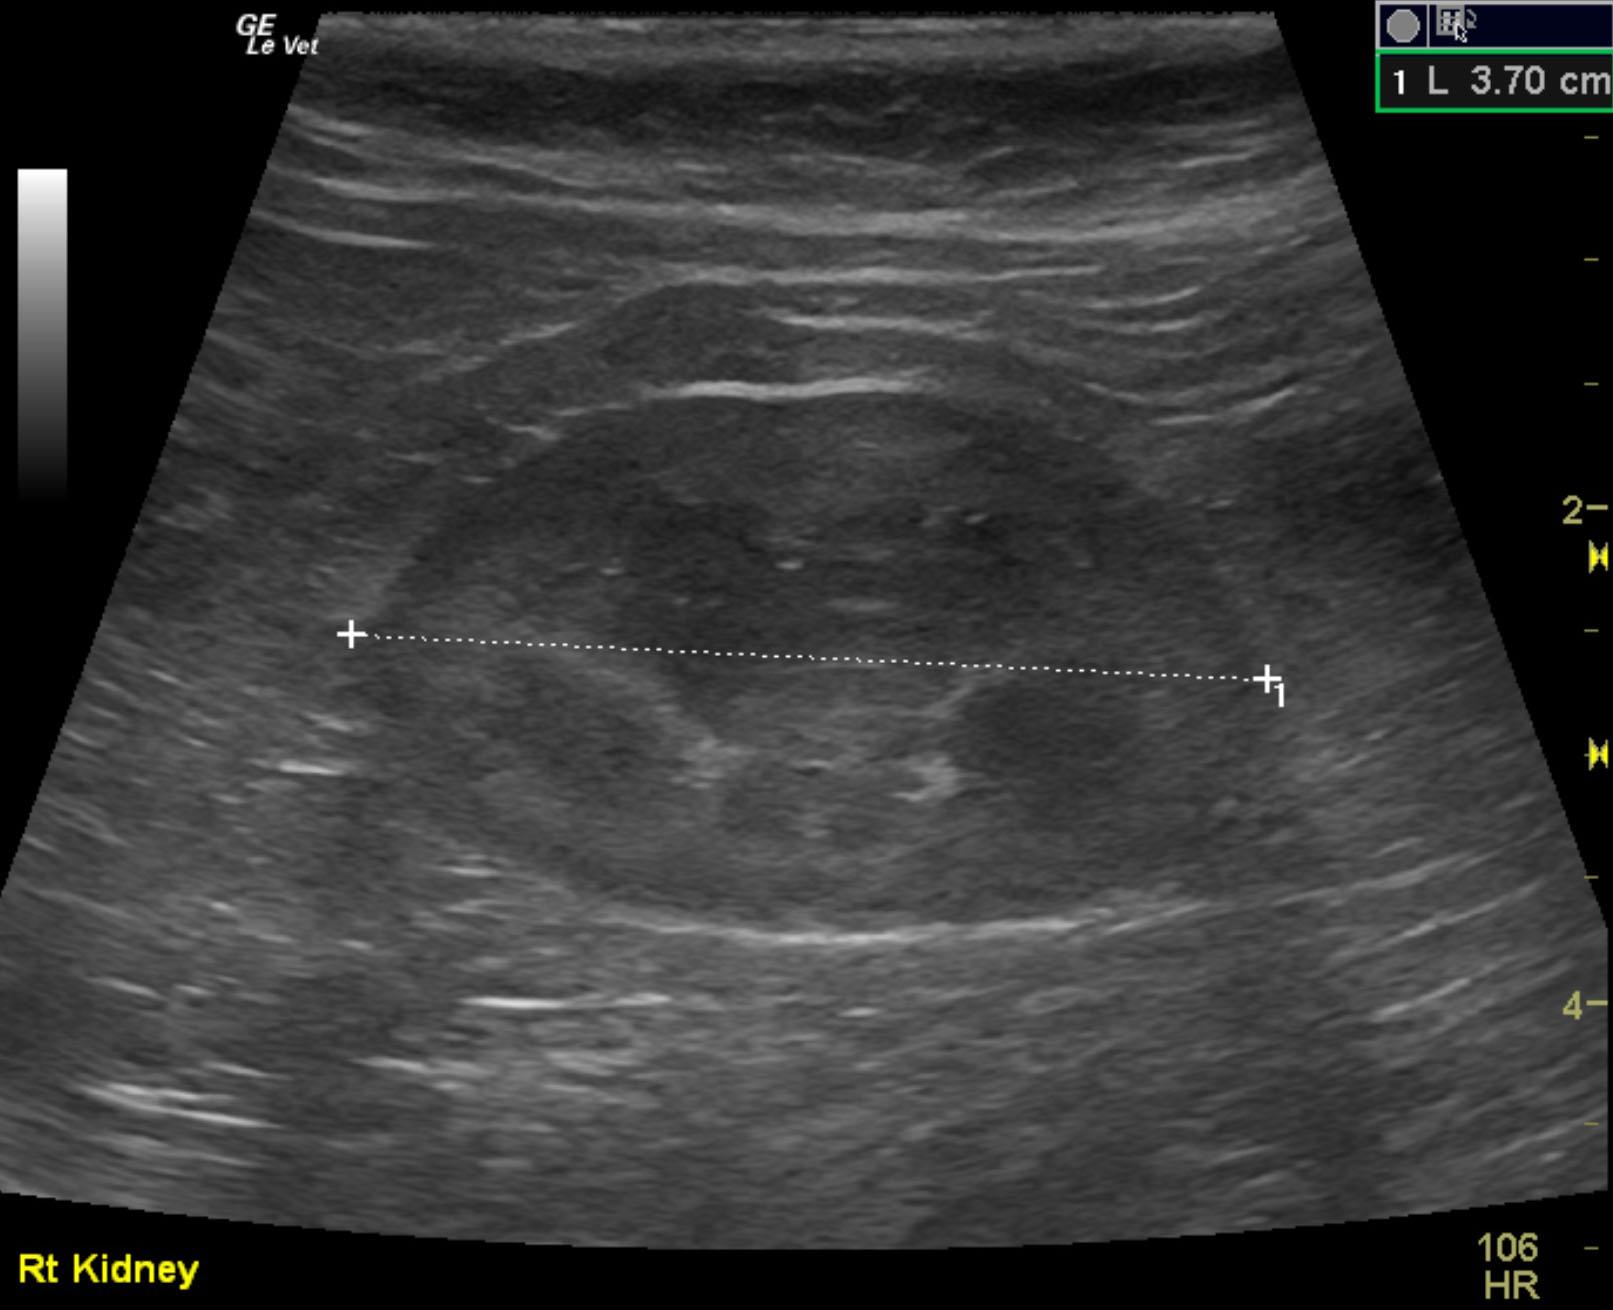

A 2-year-old neutered male DMH cat was presented for urethral obstruction and a possible mass dorsal to the urinary bladder. The cat also had a 5-day duration of diarrhea.